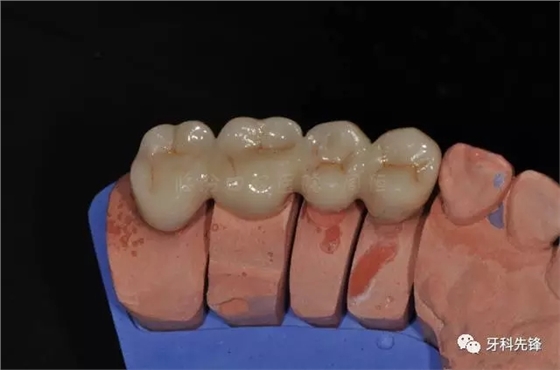

圖13牙體預(yù)備模型照

圖14臨時牙

圖15臨時牙咬合照